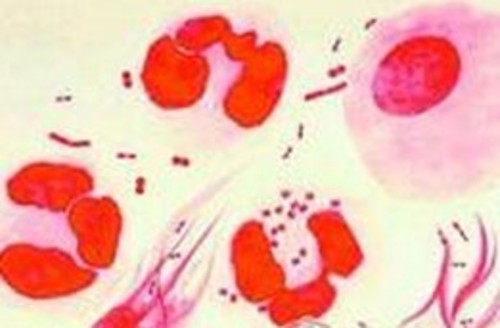

治愈淋病哪种方法好?淋病在我国的发病率非常高,它是一种古老而又常见的性传播疾病,主要是通过性行为直接传染,感染上该病后不仅危害到患者的身体健康,同时对患者的心灵造成了极大的创伤。所以,患上淋病好及早治疗。但是,生活中有不少淋病患者治疗后出现复发的迹象,那么治愈淋病哪种方法好呢?针对这个问题,下面我们具体来了解一下。

3、重复感染:即患者与未经治疗的淋病患者进行性交而再次感染上淋病、梅毒。所以淋病、梅毒患者应彻底治疗,并主张一方得病,夫妻双方应同时治疗,直至本人及配偶都治好以后方可恢复性生活。可以说,淋病、梅毒并非治不好,关键是没有选好药。